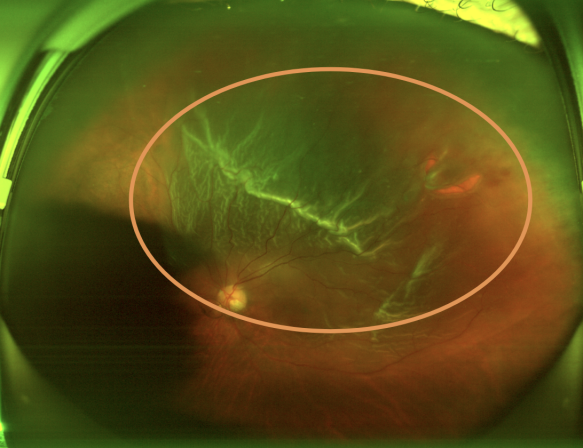

(图一:左眼孔源性视网膜脱离术前术后如图所示)

入院后进一步检查发现,付先生有20多年高血压病史。左眼眼底视神经乳头边界清晰、颜色偏淡红,视网膜血管走行正常;但左眼颞上方位有一个约瞳孔大小的马蹄形裂孔,该处视网膜已呈青灰色隆起,累及黄斑区,所幸其余部位视网膜平整。眼部B超还提示双眼玻璃体轻度混浊,右眼玻璃体后脱离,左眼可疑少量出血。最终明确诊断为“左眼孔源性视网膜脱离”。